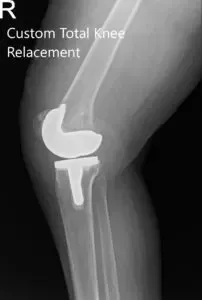

Postoperative X-ray of the right knee showing AP and Oblique views.

He had an excellent recovery from their total knee replacement in the postoperative period. He was able to walk with support the same day of the surgery. The pain was managed with oral medications and was started on aspirin for DVT prophylaxis. On his subsequent visit, the staples were removed and the range of motion was found to be full. He was stressed on the importance of strict control of blood sugar levels and compliance with physical therapy.

Subsequently, the patient followed three months later stating complete relief of pain in the right knee and decreased pain on the left side. He was planning to travel to Phoenix on his grandson’s graduation and was happy with the prospect of doing it without pain. He regularly follows up and will plan for the left knee replacement in the future if required.